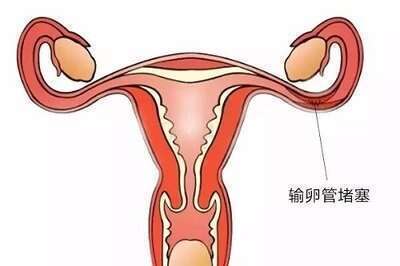

输卵管堵塞是指输卵管内受到阻碍,无法正常传递卵子的情况,这种状况可能会阻碍受孕。据研究表明,有些输卵管的情况下,没有堵塞的现象。比如,根据“生化”这种检查手

出现输卵管堵塞的原因有多种,具体以下几点一起来看看。 ① 出现月经不调 输卵管发生炎症,由炎症引发的堵塞,会对卵巢功能造成损害,从而导致月经不调。 ②

双边输卵管堵塞(bilateraltubalocclusion)是一种常见的不孕症,它是指双侧输卵管有堵塞,卵子不能从卵巢通过输卵管传递到子宫,从而导致不能